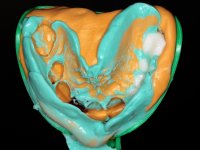

O estudo imagiológico para a colocação dos implantes, começou com a realização em laboratório de uma guia com dentes em sulfato de bário. Esta guia foi colocada em boca conjuntamente com marcas de referência coladas aos dentes, também em sulfato de bário. A guia foi estabilizada com cera mole. A TAC foi realizada com estas referências colocadas em boca. Após a realização da TAC foi feita uma impressão de arrasto em silicone. Esta impressão foi vazada a gesso em laboratório e posteriormente digitalizada. A digitalização do modelo com as referências foi sobreposta á imagem da TAC, permitindo uma planificação apurada na colocação dos implantes. Na planificação foi decidido colocar 2 implantes no local dos dentes 2.3 e 2.4 evitando-se a zona do 2.2 com pouco osso e o seio maxilar. Este estudo deu origem a uma guia cirúrgica que orientou a colocação dos implantes. Durante o período de osteo-integração a paciente utilizou a prótese removível rebasada com acondicionador de tecidos. A guia cirúrgica mostrou-se também útil na exposição dos implantes mostrando a sua localização precisa e orientando a incisão. A impressão definitiva foi realizada utilizando a técnica de moldeira aberta após eliminação do attachment. No laboratório foi confeccionada uma ponte metalo-cerâmica de 3 elementos com o elemento 2.2 em suspensão. A ponte após verificação e aprovação foi cimentada. A reabilitação apesar de pouco extensa (sem o elemento 2.6) mostrou-se capaz estetica e funcionalmente.